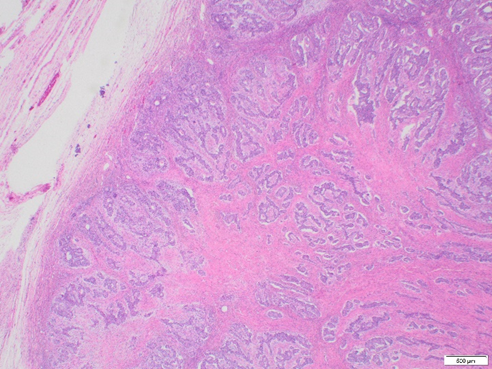

A 60-year-old woman presents with urinary symptoms, abdominal distension and bloating. A CT scan shows a large pelvic mass. A bilateral salpingo-oophorectomy with omentectomy is performed and reveals a 27.5 x 22.5 x 17.9 cm white, firm, and solid mass in the left ovary. Immunohistochemical staining shows positivity with pan-cytokeratin, CAM5.2, ER, PR, WT1, and PAX8 (patchy). Beta-catenin shows nuclear patchy staining. Calretinin, inhibin, and SF-1 are negative in neoplastic cells. The neoplastic cells are negative for GATA3, TTF-1, CDX2, INSM1, chromogranin, and synaptophysin.

Endometrioid carcinomas are morphologically heterogeneous, with a spectrum of appearances similar to those seen in endometrioid carcinomas of the uterus, potentially constituting a diagnostic pitfall (Malpica, 2016). On rare occasions, endometrioid carcinoma mimics sex cord-stromal tumors, a common scenario encountered in the ovary. These tumors can form solid or hollow tubules, nests, and elongated cords, such as in our case.

The distinction between endometrioid carcinoma with a sex cord pattern and a true sex cord-stromal tumor is based on recognizing this unconventional architecture and confirmation with immunohistochemical stains. The tumor is frequently positive for EMA and cytokeratins and negative for sex cord markers. Although PAX8 may be often negative, ER, PR, beta-catenin, and CD10 has been expressed most studies (Travaglino et al., 2024). Despite its unusual morphology, endometrioid carcinoma with a sex cord pattern typically behaves as a low-grade tumor and shows an excellent prognosis when confined to the ovary (Young et al., 1982).